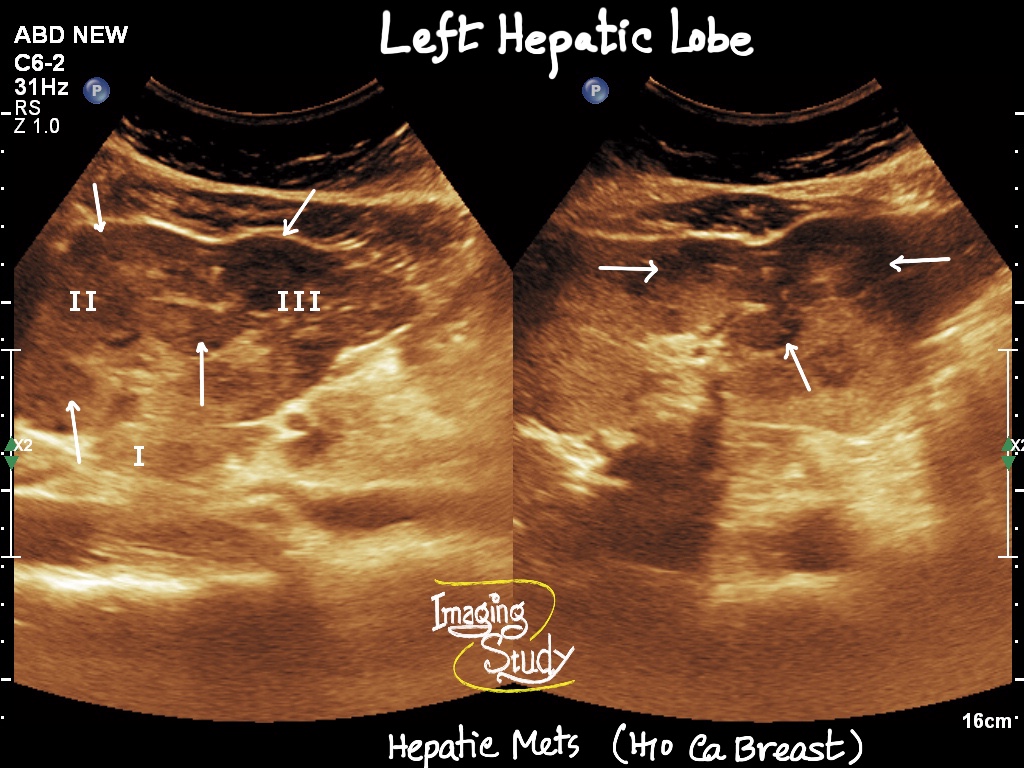

Hepatic Metastasis

Hypo or hyperchogenic space occupying lesions

Ill defined

Internal vascularity on color Doppler

May compress adjacent vasculature

Search for the primary source